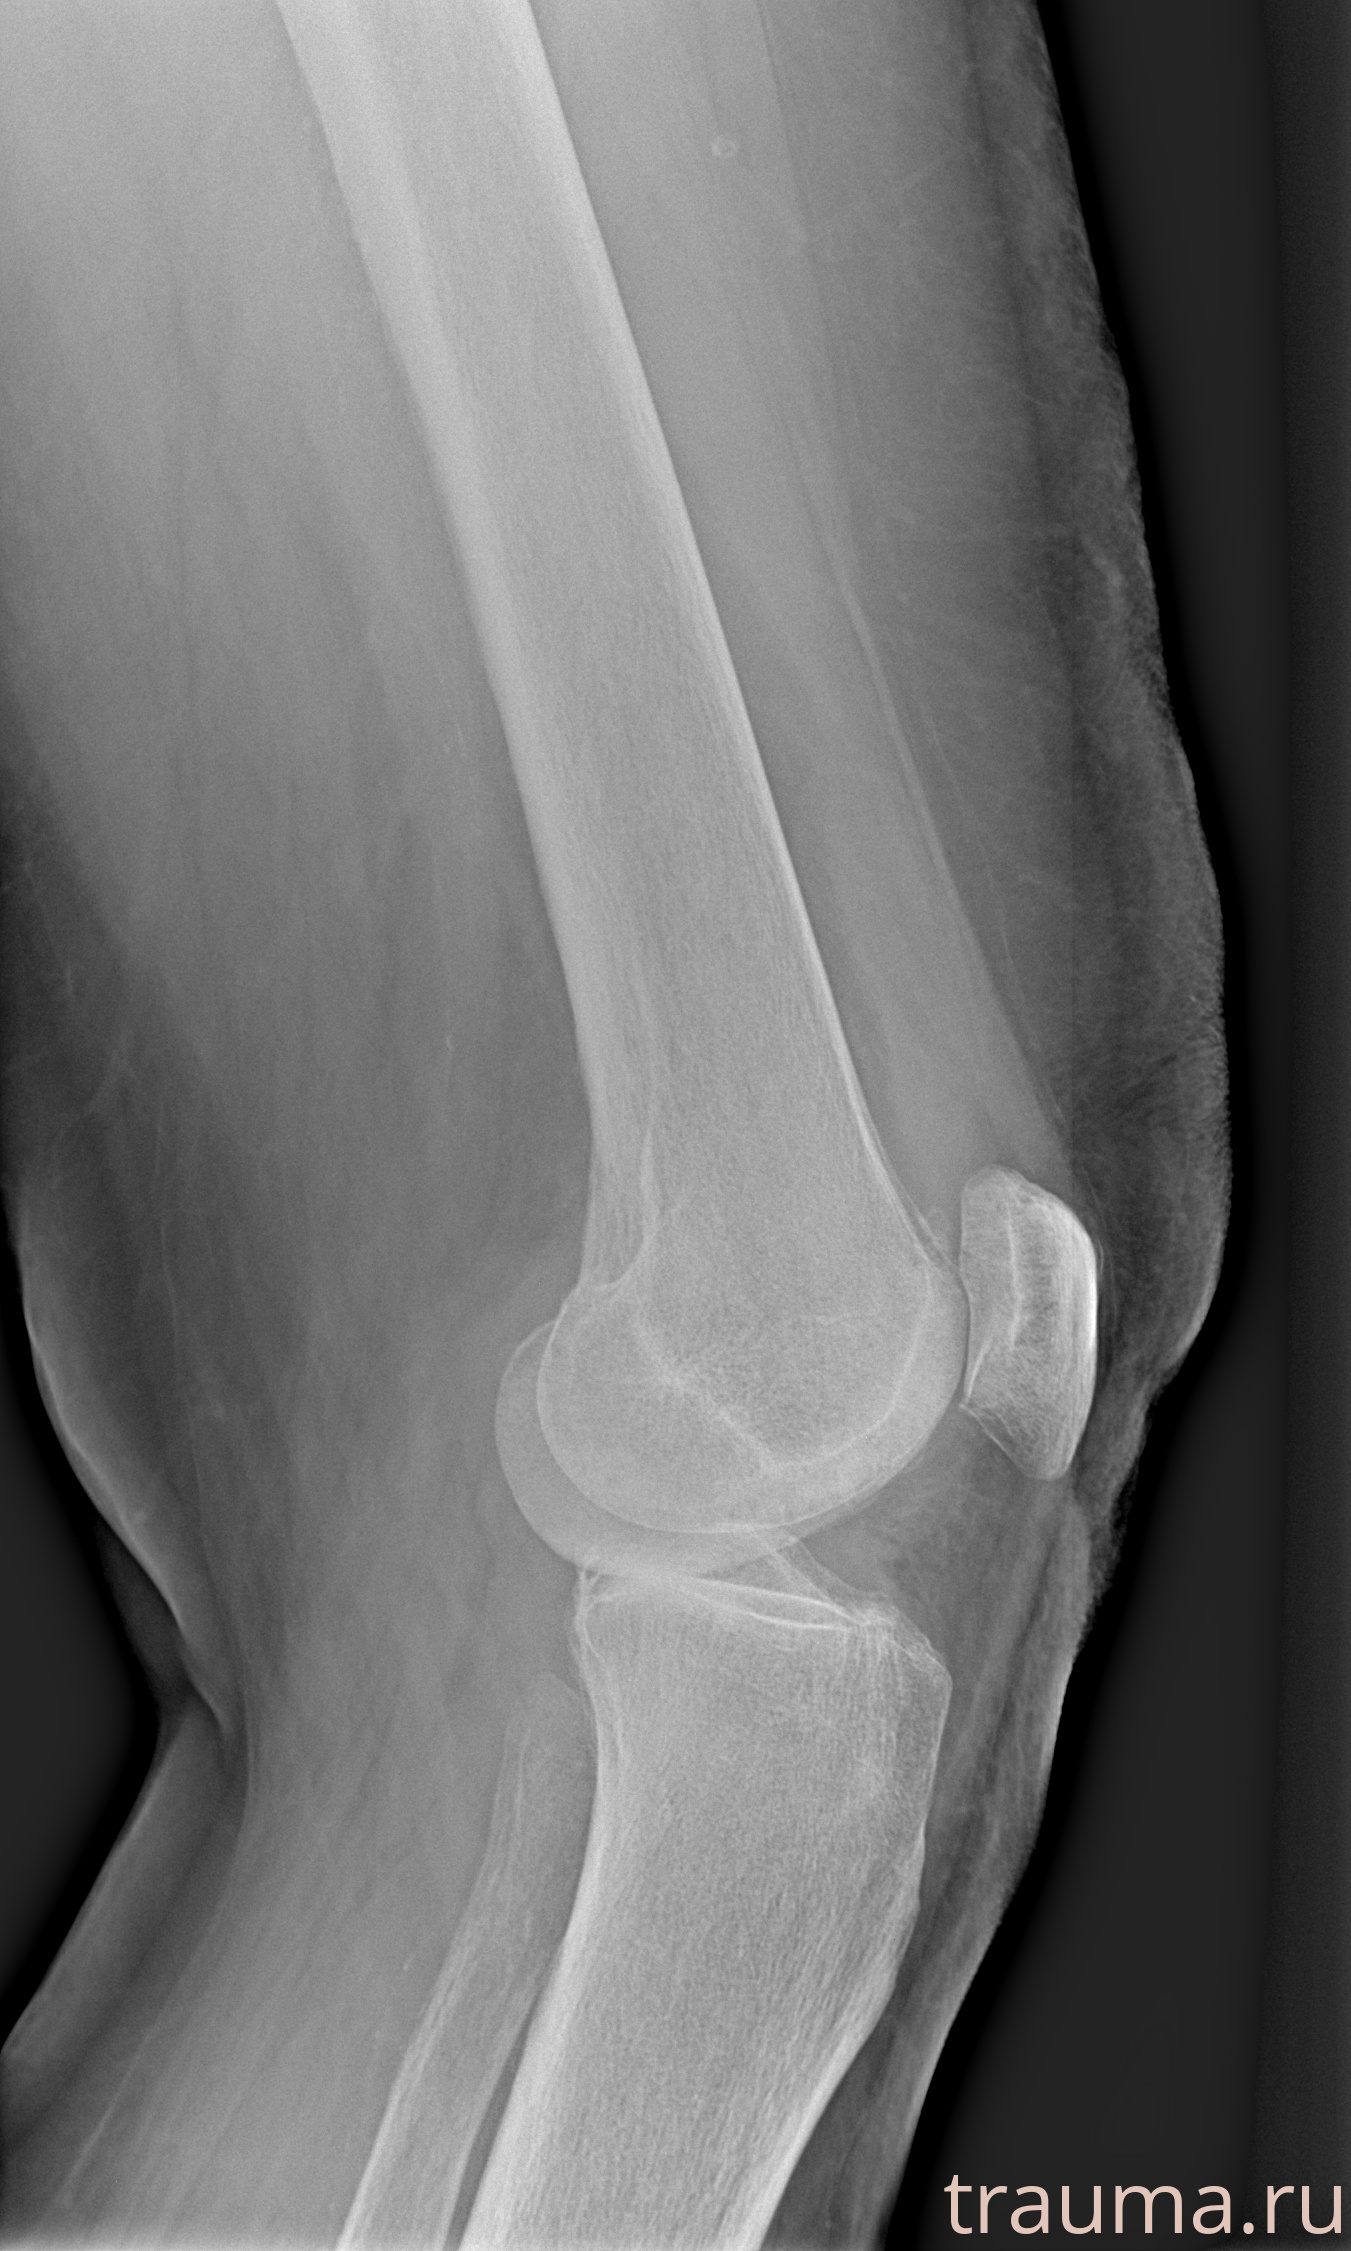

Рентген на дому: по вашему адресу приезжает врач-рентгенолог, травматолог-ортопед с мобильным рентгеновским аппаратом, проводит диагностику травмы или заболевания, делает необходимые рентгенограммы, дает рекомендации по дальнейшему лечению. Получить качественные снимки в домашних условиях возможно благодаря уникальной методике, разработанной МосРентген Центром для института  Склифосовского

при переломе шейки бедра и пневмонии от компании МосРентген Центр - партнера Института имени Склифосовского